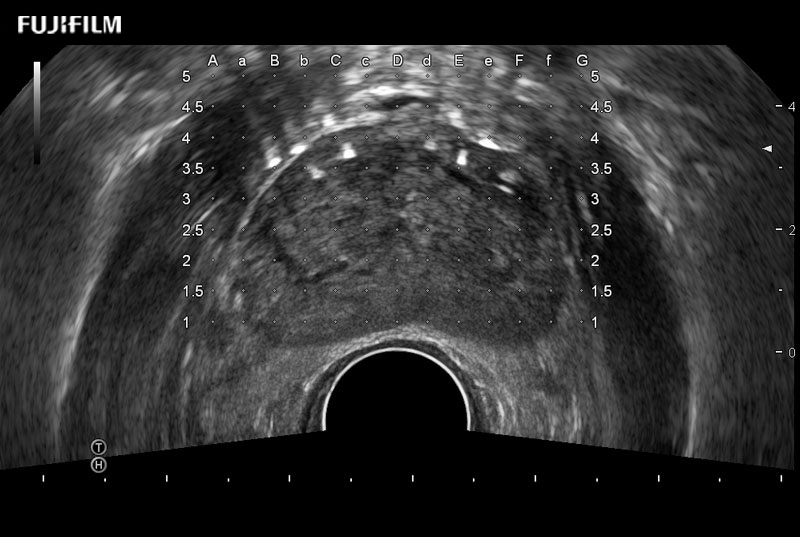

Exclusive 200° FOV end-fire prostate biopsy transducer.

Main Specifications:

Provides real-time imaging of both the sagittal and transverse planes